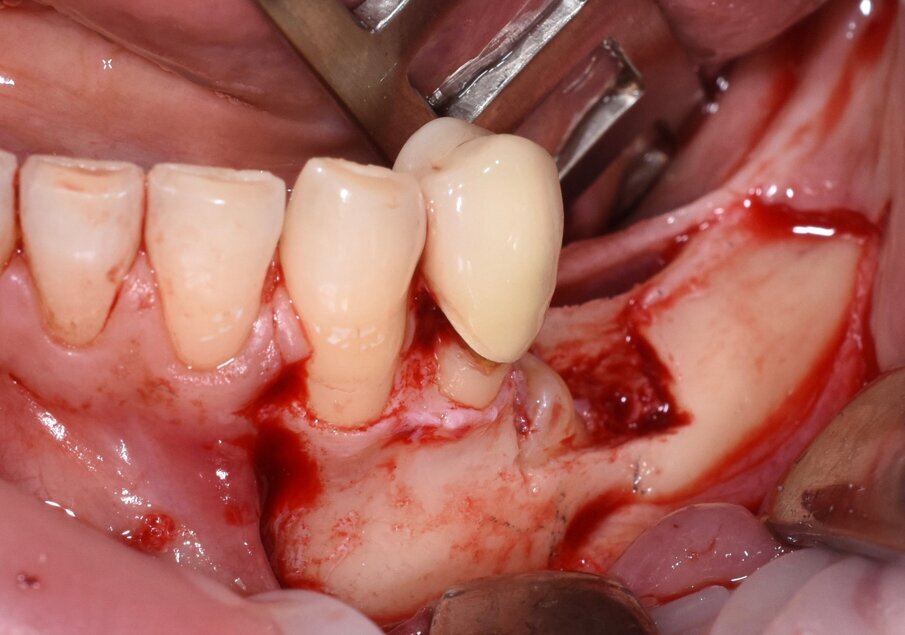

Fig. 7 - Rimozione del tassello osseo e visione della corona del 3.5.

Fig. 8 - Odontotomia eseguita con inserto piezolettrico.

Considerata la necessità di eseguire un riabilitazione implantoprotesica della sede edentula si è resa necessaria l’avulsione dell’elemento incluso con tecnica piezoelettrica che ci ha permesso di ridurre al minimo l’osteotomia e preservare l’integrità del nervo la cui emergenza si trovava esattamente in corrispondenza della corona del 3.5 (Figg. 3-9).